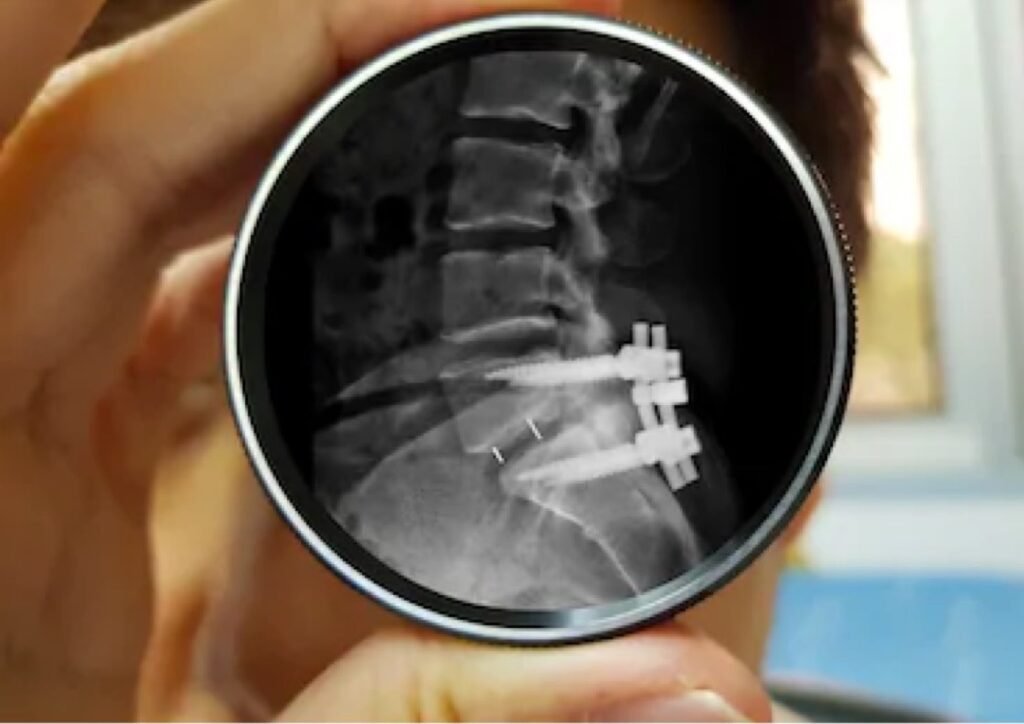

Surgical Treatment

Surgery is recommended when conservative treatment fails or nerve compression is severe.

Modern techniques provide faster recovery and reduced pain.